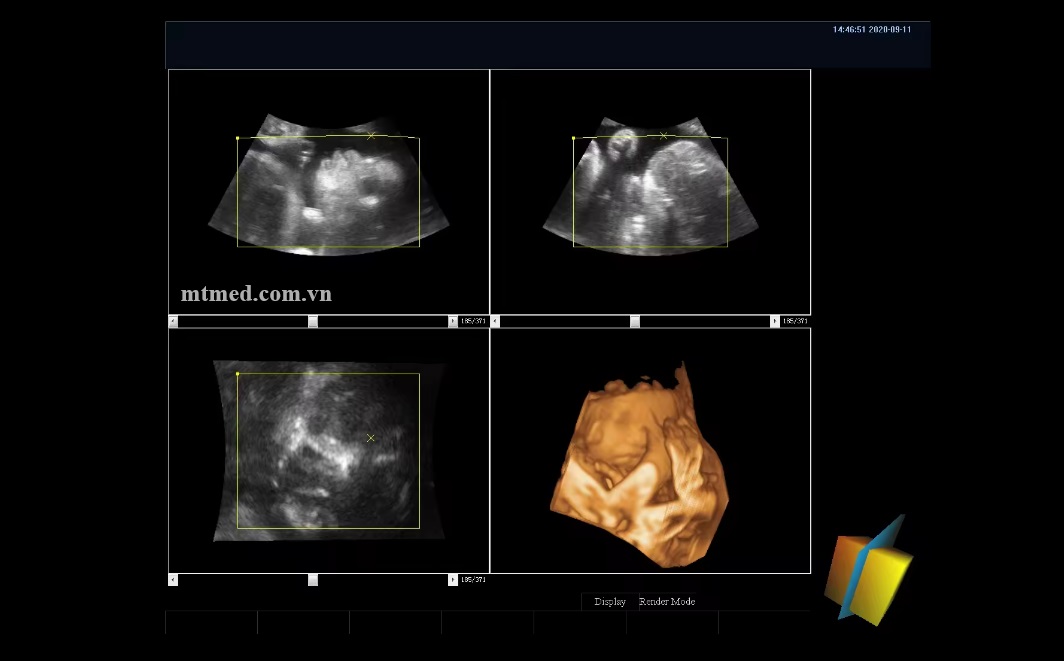

Công nghệ Máy siêu âm 4D cho động vật là một sự nâng cấp từ công nghệ 3D, cới khả năng tạo ra hình ảnh không chỉ theo ba chiều mà thêm chiều thứ tư là thời gian, cho phép quan sát các chuyển động của cơ quan cấu trúc bên trong cơ thể một cách liên tục.

*quan sát thai nhi trong bụng động vật, đánh giá tình trạng phát triển và phát hiện các dị vật sớm.

*Hình ảnh rõ nét và chi tiết : giúp cung cấp cái nhìn trực quan về cấu trúc và chuyển động của các cơ quan bên trong cơ thể động vật.

*Thời gian thực: cho phép bác sĩ thú y đánh giá ngay lập tức tình trạng của động vật và đưa ra quyết định điều trị nhanh chóng.